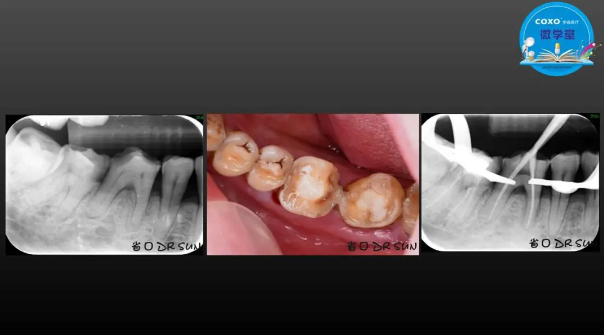

主講:孫書昱

主任醫(yī)師,牙體牙髓副主任, 廣東省口腔醫(yī)院牙體牙髓科 主任醫(yī)師。2003年碩士研究生畢業(yè),研究方向為牙體牙髓病學,擅長于牙體牙髓病的診斷、齲齒、牙髓炎、根尖周病的治療以及前牙美容修復。